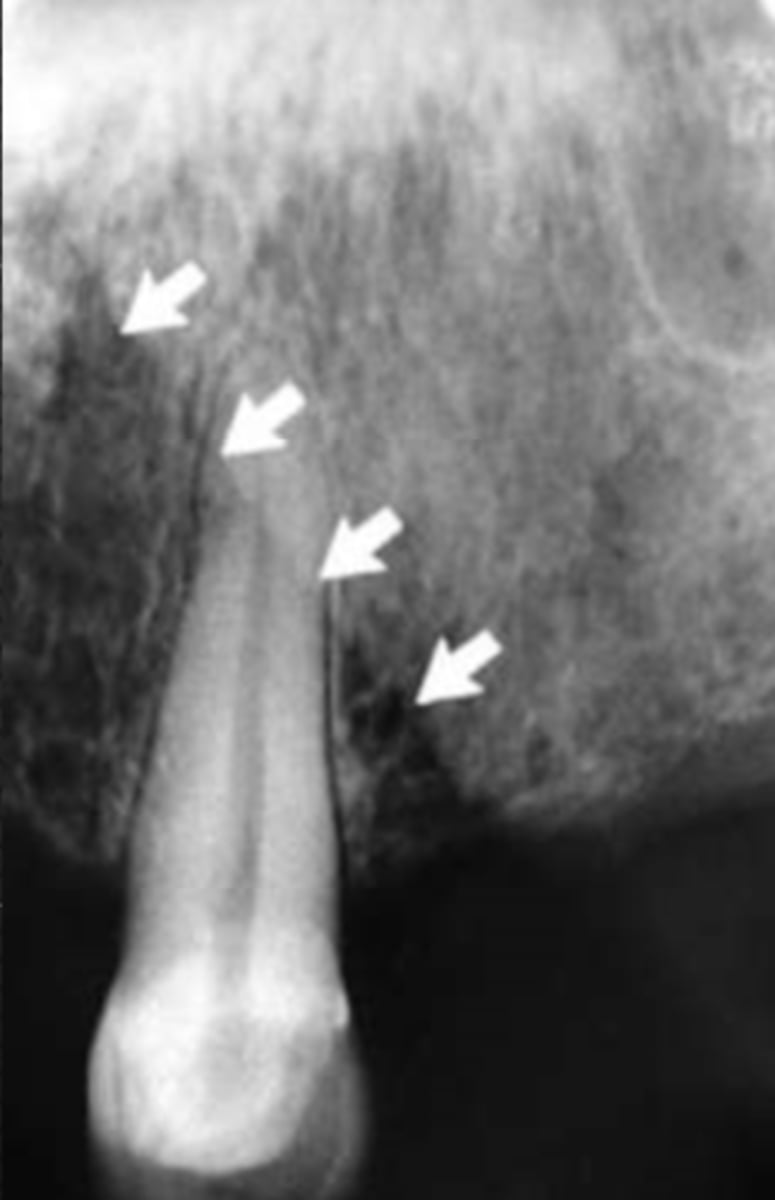

Mandibular canal

Identify the structure

Identify the radiolucent structure

What is causing the thick radiolucent line surrounding the dotted line?